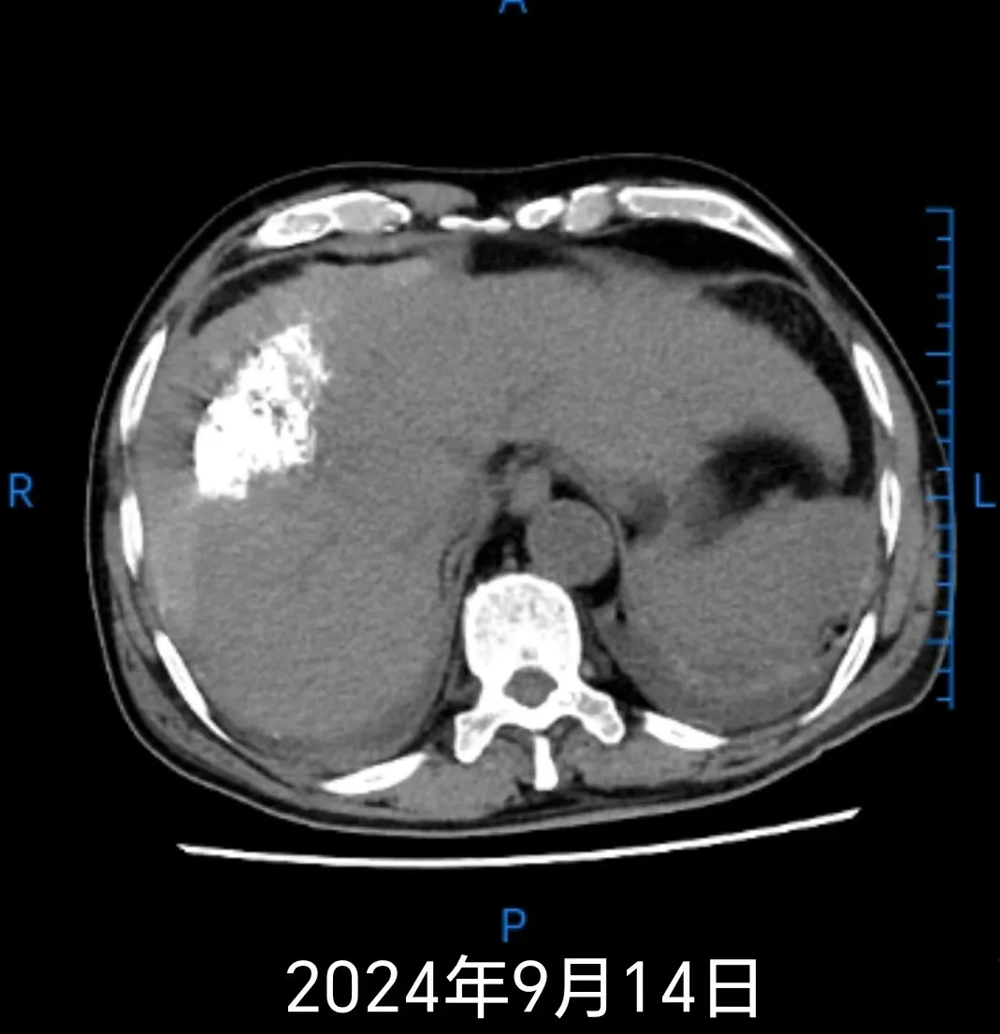

患者熊某,男,67岁,因持续3小时腹痛于2024年9月11日23时30分就诊于武宁县人民医院北院。急诊CT检查提示:肝硬化,肝右叶占位破裂出血(肝周、脾周积血)可能性大,左肾结石与血管钙化待鉴别,盆腔积液。结合床旁彩超结果:肝内占位性病变、肝右前间隙团絮状稍高回声、腹腔中量积液,综合考虑为肝内占位性病变合并破裂出血。诊断为肝癌破裂出血、失血性休克,因病情危重,患者急诊转至人民医院院区肿瘤消化科住院治疗。

鉴于患者出血量大、生命体征不平稳,经与家属充分沟通并签署手术知情同意书后,于2024年9月12日03时急诊在DSA下行经导管肝动脉栓塞术。术后患者生命体征平稳。9月14日复查CT显示肝肿瘤及介入术后改变,建议随诊复查或MRI检查,同时提示腹盆腔积血。